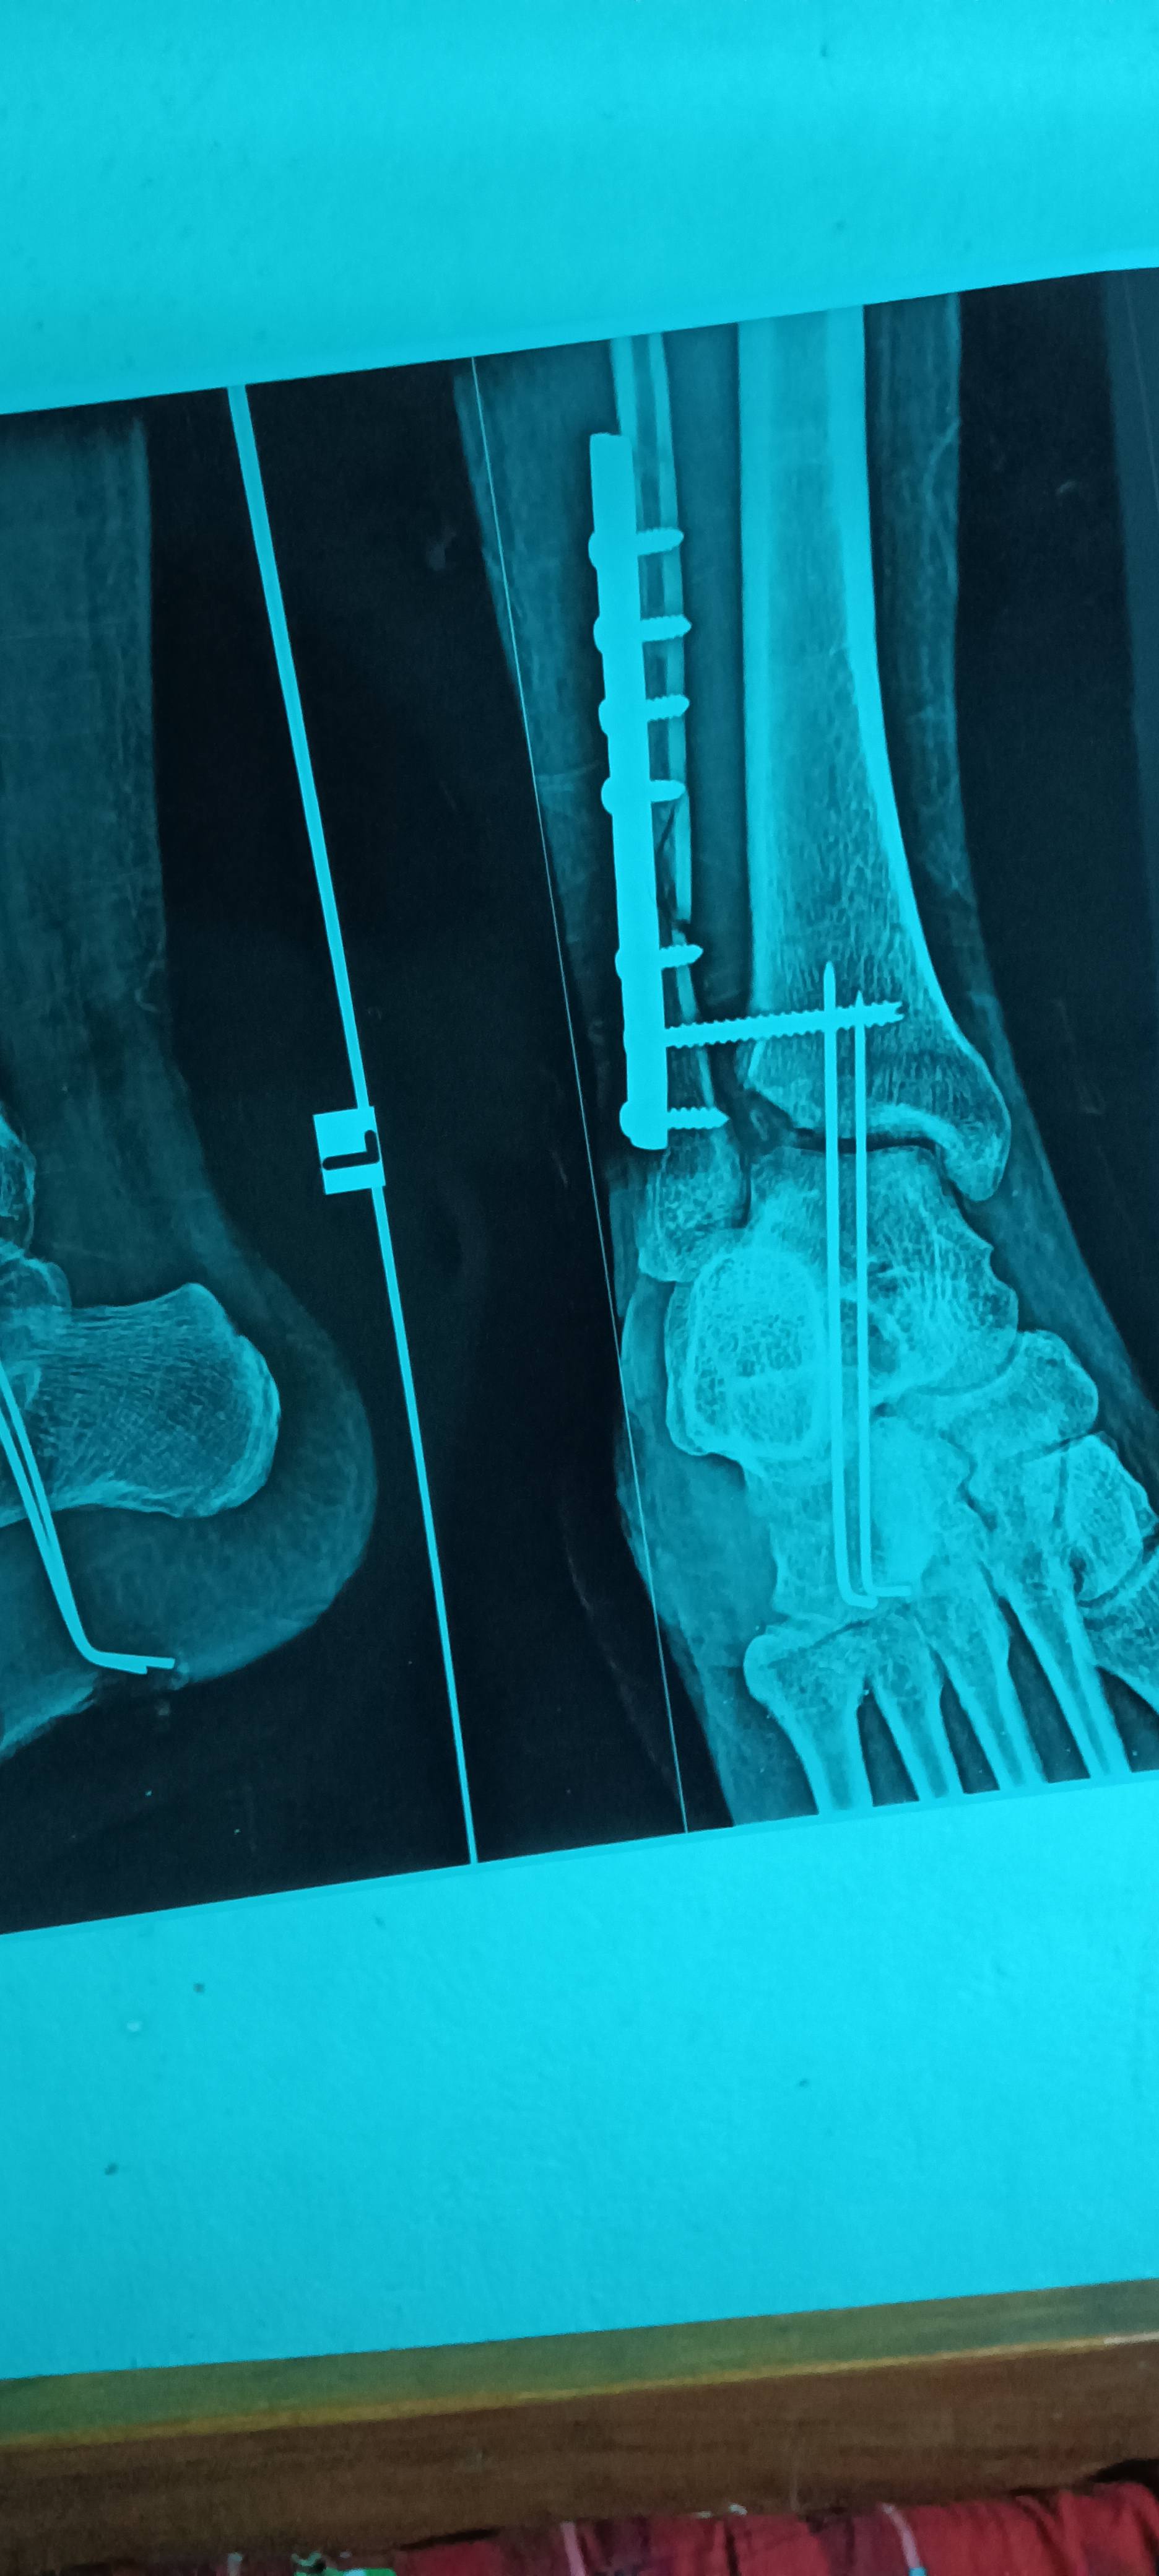

Sir tibia bone ka kuch niche wala part Tut kar lost ho gaya hai usse agar koi problem hai to bataye